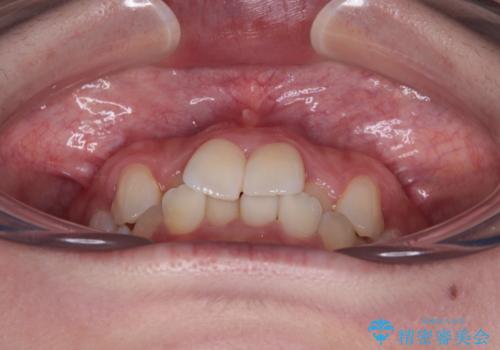

前歯のクロスバイト 裏側に隠れた歯をワイヤー装置で短期間治療

- 上顎前歯のクロスバイトを気にして来院された患者様です。

ワイヤー矯正でもマウスピース矯正でも対応可能でしたが、マウスピースによる自己管理に一切の自信がないとのことで、ワイヤー装置にて矯正治療を行うこととしました。